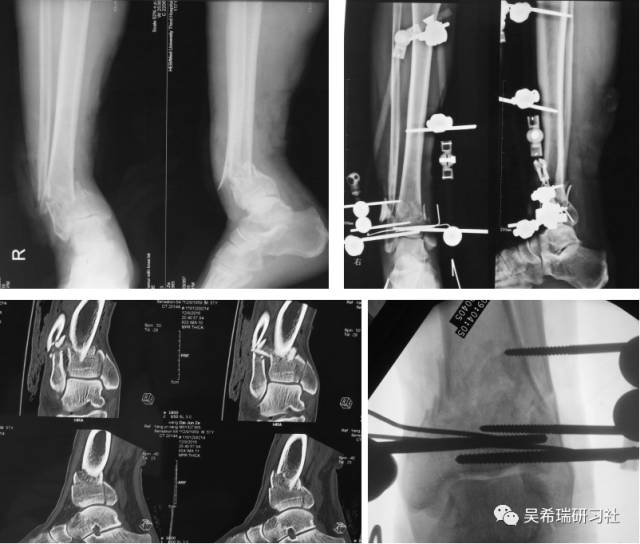

男  43岁 从2米处摔伤  开放性Pilon骨折

TIPS:关节内骨折非跨越关节固定技术一期应用骨水泥 + 开放植骨技术腓骨克氏针固定技术截骨矫形胫骨近端取骨技术